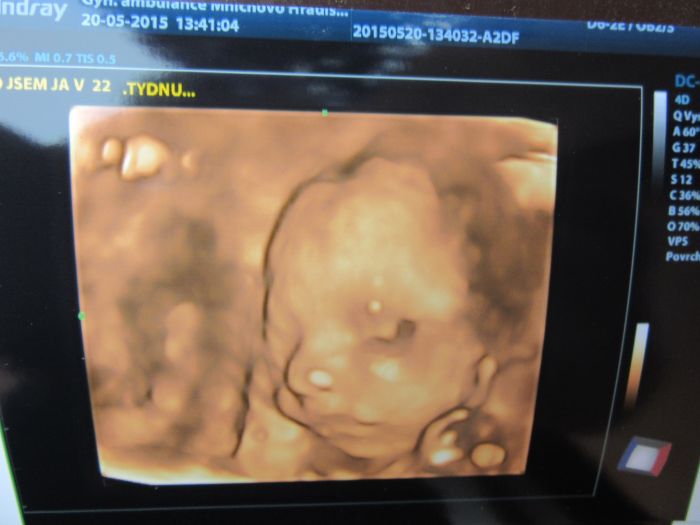

Ahojky, tak dneska jsme byli s manželem na 3D a máme potvrzenou malou fešandu. I přesto, že jsme si přáli kluka tak nakonec jsem spokojená, že to bude holčička. Doktor nám taky řekl, že je vše v pořádku a to je to hlavní. Přikládám fotečky, jsem z malý opravdu nadšená.